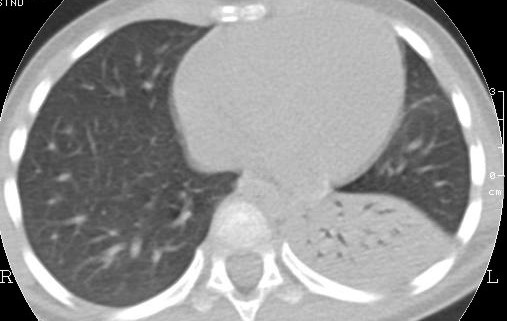

La TAC, eseguita a risoluzione del terzo episodio infettivo, metteva in luce la presenza di lesione malformativa, altrimenti non visibile in radiologia convenzionale (Figura 2).

Figura 2 |